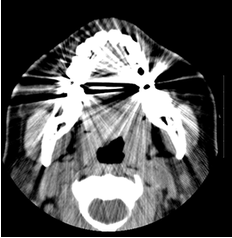

避免产生影像伪影

随着医学技术的发展,CT及核磁共振在疾病的诊断和治疗扮演着重要角色。而口腔贱金属材料会在图像成像时形成伪影,干扰医生正常诊断。全瓷牙由于不含金属,不会影响各种影像学检查,是口腔应用中的首选材料。

图片

金属冠产生的放射状伪影